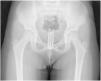

There was no history of trauma, sexual abuse, soreness, urinary or rectal complaints. The symptoms did not respond to hygiene measures and appropriate antibiotic therapy. The physical examination revealed no abdominal tenderness and normal external genitalia, with no lesions or active discharge. However, there was a bloody and foul-smelling discharge on the sanitary pad. A pelvic ultrasound scan (Fig. 1) and a pelvic radiograph (Fig. 2) revealed the presence of a foreign body measuring 40×10mm. The patient underwent vaginoscopy under anaesthesia for removal of a hair clip.